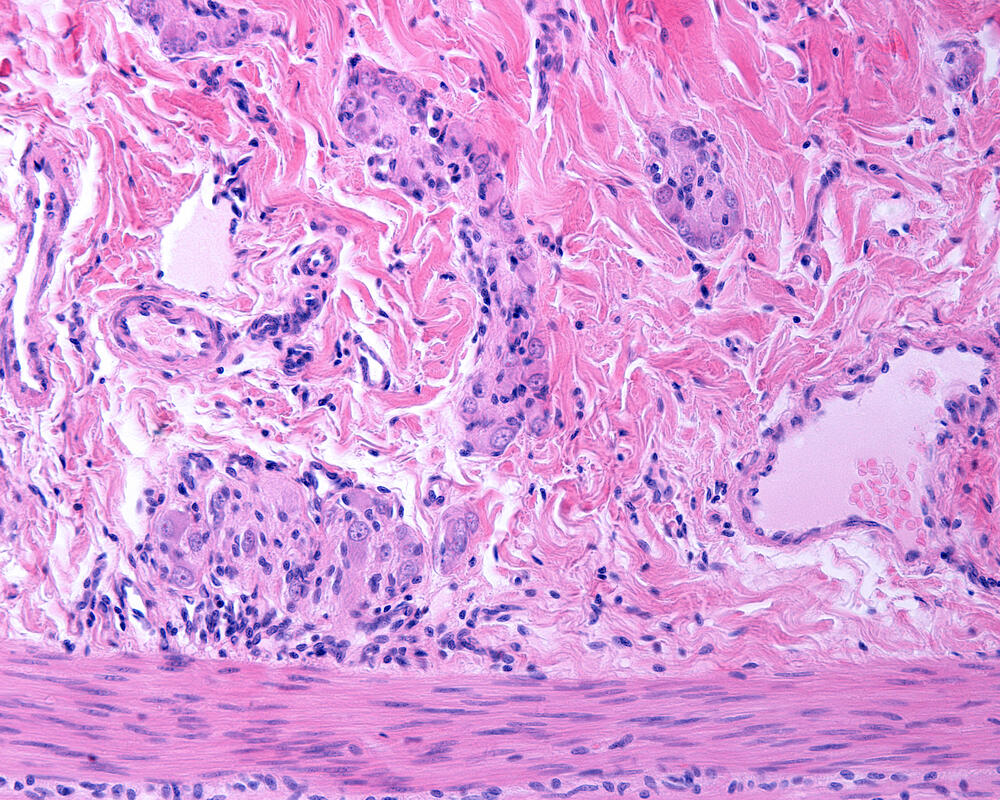

Ulcerative colitis (UC) is a disease that causes ulcers and inflammation in the digestive tract. Common symptoms include diarrhea, abdominal pain, cramping, weight loss, fatigue, fever and more, which can sometimes lead to life-threatening complications. There is currently no known cure for this condition, but several new treatments can reduce and control symptoms.